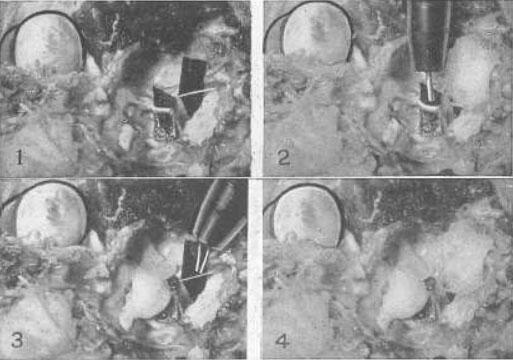

Рис. 22. Эксперимент на примере глаза кошки, демонстрирующий то, что четвертый нерв, который снабжает только верхнюю косую мышцу, является точно таким же нервом аккомодации, как и третий, и что верхняя косая мышца, которую он снабжает, есть мышца аккомодации

1 Оба нерва были выведены наружу возле их основания в головном мозге, и полоска черной бумаги была вложена позади каждого, для того чтобы изображение можно было увидеть. Четвертый нерв это тот, что поменьше. Верхняя косая мышца была перемещена путем подгибания. Так как эта мышца всегда недоразвита у кошек, то до тех пор, пока ее натяжение не усиливают, аккомодация у этих животных не воспроизводится. Стимуляция одного или обоих нервов импульсным током способствовала возникновению аккомодации.